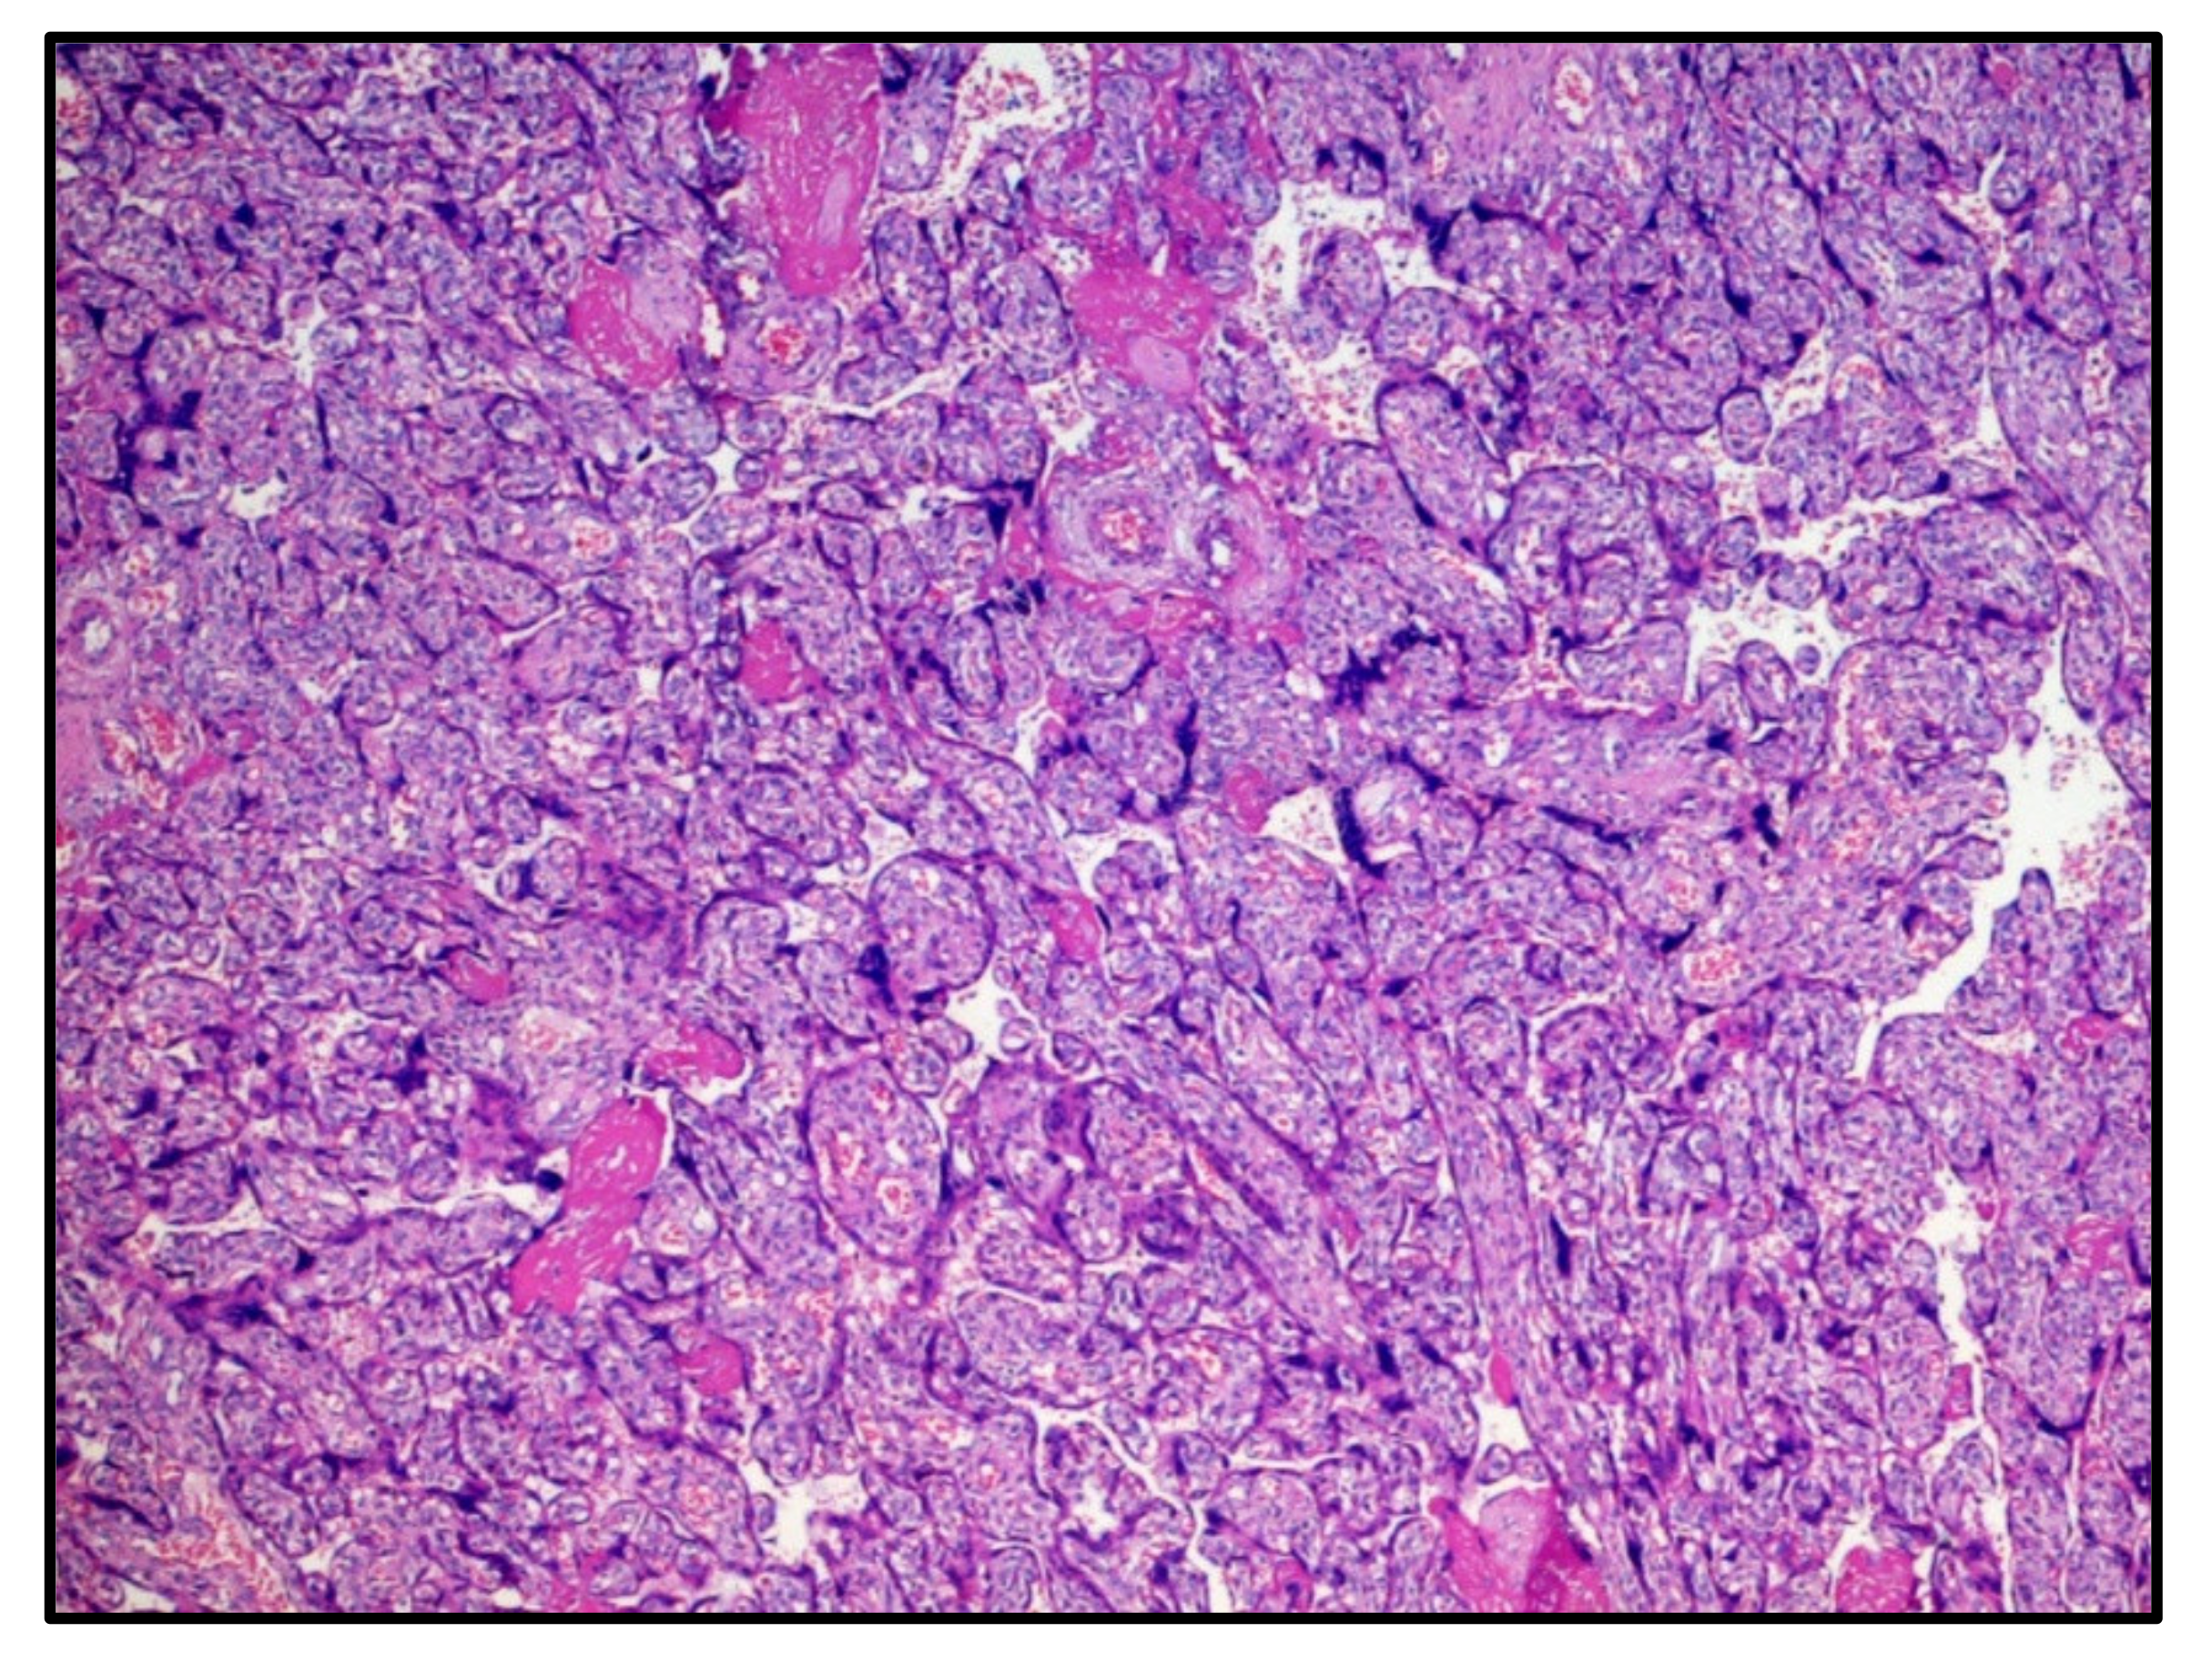

The first chorionic disc corresponded to the gestational age and presented very large areas of intervillous fibrinous deposition (Figure 1) with the presence of numerous perivillary histiocytes. Minor recent infarct foci were also described, while umbilical cord and amnio–chorionic membranes were completely normal. The immunohistochemical reaction for the SARS-CoV-2 protein S1 was strongly expressed both in the syncytiotrophoblast cells and in the perivillary histiocytes described in H&E (Figure 2).

Figure 1. Histological features of the first chorionic disc: deposition of intervillous fibrin and chorionic villi corresponding to the gestational age (30 weeks). Hematoxylin-Eosin, 10×.